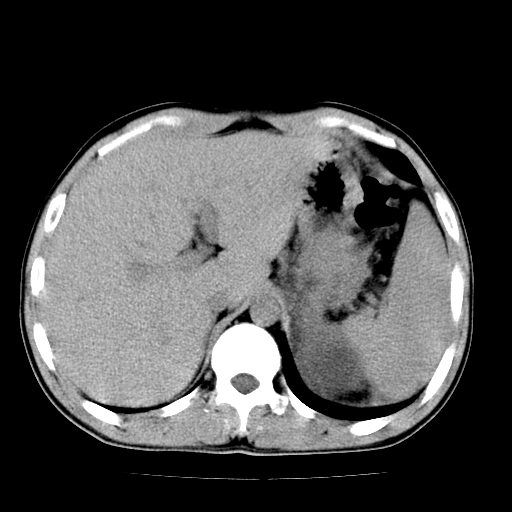

以下是引用天南地北在2007-4-30 13:36:00的发言:[br]支持慢性胰腺炎伴有假性囊肿

以下是引用andymaomao在2007-4-30 14:28:00的发言:[br]支持:1.慢性胰腺炎并假性囊肿形成可能;[br] 2.左肾形态稍增大,旋转不良。